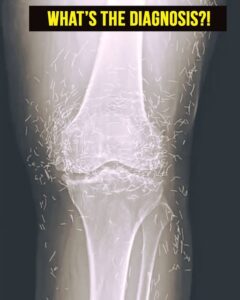

In this woman’s case, imaging studies revealed multiple gold needles embedded deep within her knee joints. Radiologists were surprised by the density and number of retained objects, which created both clinical interest and concern.

Modern imaging techniques, including X-rays and MRIs, can detect these embedded needles. Radiologists must consider retained metal when interpreting images, as it can interfere with diagnostic clarity and obscure underlying conditions.